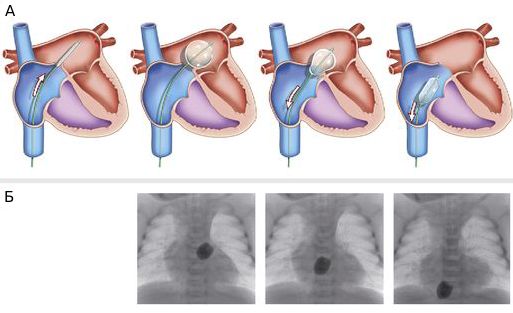

К сожалению, очень часто поддержания проходимости артериального протока недостаточно для адекватного смешивания крови, и некоторые пациенты, особенно те, у которых нет дефекта межжелудочковой перегородки, поступают в профильный стационар в тяжёлом, а иногда критическом состоянии, несмотря на то, что артериальный проток работает. Это состояние бывает вызвано обструктивным сообщением на уровне межпредсердной перегородки (открытым овальным окном). В таком случае необходимо экстренно выполнить операцию баллонной атриосептостомии, или процедуру Рашкинда. Это вмешательство проводится в ангиографической операционной под рентгенологическим и эхокардиографическим контролем. Смысл операции заключается в проведении катетера со сдутым баллоном на конце через межпредсердную перегородку в левое предсердие, после чего баллон раздувается.

Схематическое (А) и рентгенографическое (Б) изображения баллонной атриосептостомии

Убедившись, что баллон находится в левом предсердии, хирург резко тянет катетер на себя, тем самым разрывая межпредсердную перегородку. Хоть и описание операции звучит очень страшно, процедура Рашкинда крайне редко приводит к развитию каких-либо осложнений.